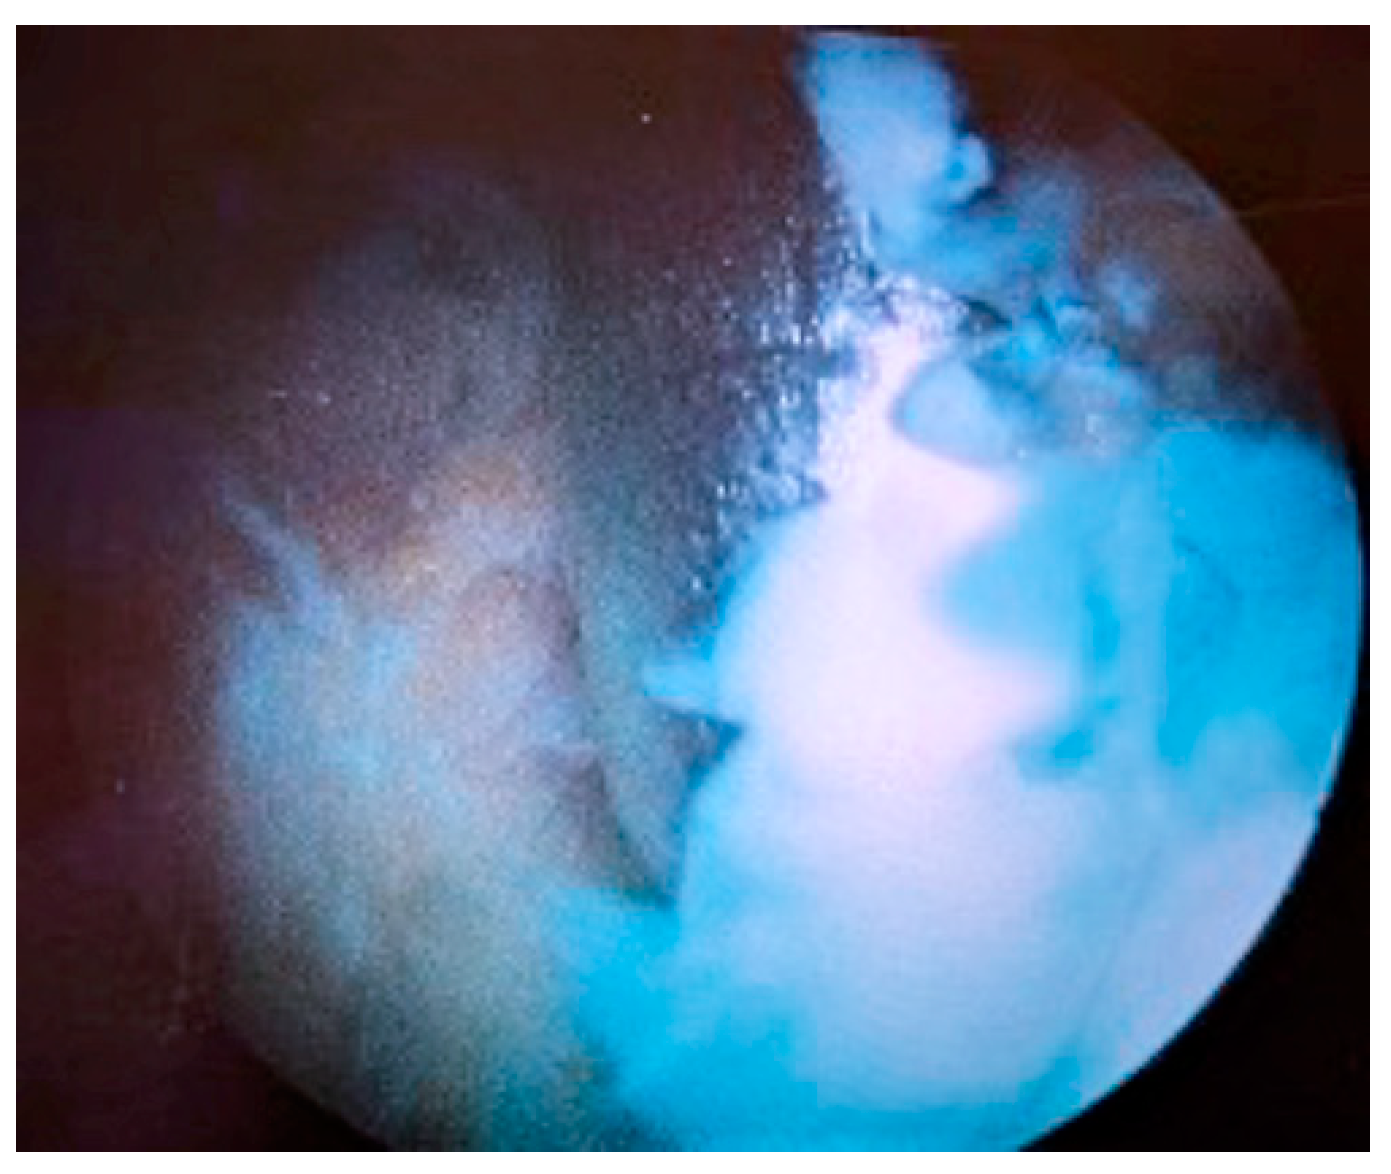

| Stage I | Opacity of fluid, redness of the synovial membrane, possible petechial bleeding, no radiological alterations |

| Stage II | Severe inflammation, fibrinous deposition, pus, no radiological alterations |

| Stage III | Thickening of the synovial membrane, compartment formation (“sponge-like” arthroscopic view, especially in the suprapatellar pouch), no radiological alterations |

| Stage IV | Aggressive pannus with infiltration of the cartilage, possibly undermining the cartilage, radiological signs of subchondral osteolysis, possible osseous erosions and cysts |